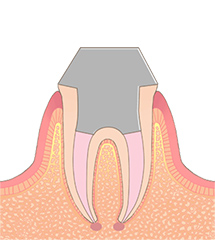

C4残根

虫歯によって、歯のほとんどが溶かされてしまった状態です。残しておくと、虫歯の巣になってしまうため、抜歯の必要があります。痛みがない場合がほとんどですが、痛みがないからと言って放置すると、ある日突然痛みだしたり、腫れたりすることがあります。